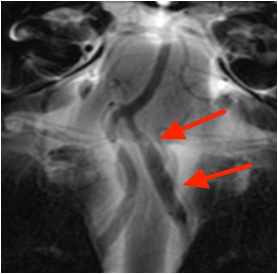

椎骨動脈解離の症例

元々片頭痛のある50代の女性です。朝起きた際に、左の首に強い痛みを感じました。寝違えたかと思い、首を少し曲げたところ、痛みはさらに強くなりました。翌々日になっても痛みが続いていたため、横浜脳神経内科を受診しました。MRA検査を行ったところ、

左椎骨動脈(左の首から後頭部へ行く血管)が不規則に膨らんでおり、動脈瘤を形成していることが分かりました。

くも膜下出血を合併する危険性があるため、血管内治療のできる専門病院へ紹介させていただきました。